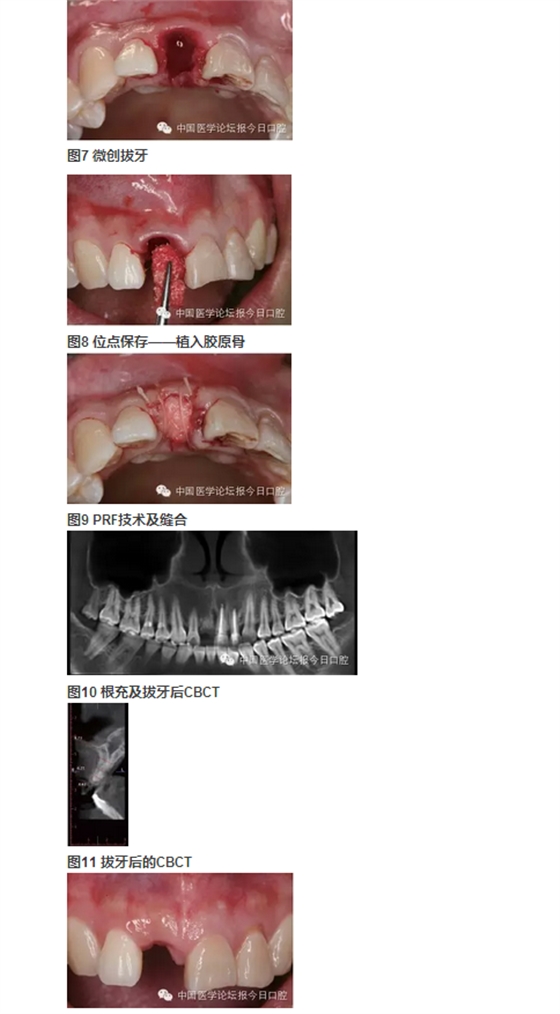

北京大學(xué)口腔醫(yī)院種植科 在唇側(cè)和舌側(cè)牙槽突骨板骨折的病例中,唇/舌側(cè)牙槽突發(fā)生相應(yīng)的骨吸收。長期的臨床經(jīng)驗告訴我們,唇側(cè)和舌側(cè)骨板的低位骨折,任其常規(guī)牙槽窩愈合,會導(dǎo)致三維方向的骨缺損。根據(jù)ITI機構(gòu)的SCA分類,伴有垂直和水平骨缺損的病例,則是復(fù)雜和高難度病例,美學(xué)風(fēng)險極大。即刻種植無法預(yù)防和避免骨吸收。 在本病例中,我們采用符合富血小板纖維蛋白(PRF)技術(shù)的牙槽窩位點保存技術(shù),最大限度保存局部骨量。以及采用輪廓擴增的引導(dǎo)骨再生(GBR)技術(shù)同期種植重建了種植位點的三維骨結(jié)構(gòu),通過暫時冠誘導(dǎo)穿齦輪廓和牙齦乳頭形態(tài),最終獲得患者滿意的美學(xué)修復(fù)。 女性,27歲。以“右上前牙樁冠修復(fù)11年,脫落1周”為主訴前來就診。 11年前,患者前牙外傷,于當(dāng)?shù)蒯t(yī)院行11、21、22根管治療及11樁冠修復(fù)。1周前11樁冠脫落,于多家醫(yī)院修復(fù)科就診,以“11牙槽突骨折”的診斷,無法保留11殘根,建議拔除,而前來就診。 既往體健,否認(rèn)系統(tǒng)性疾病史及藥物過敏史。 臨床檢查可見11殘根,21、22牙冠變色。前牙區(qū)咬合略緊,Ⅱ度深覆牙合。CBCT示上頜右側(cè)中切牙頰側(cè)根頸1/3骨板折裂。21、22牙冠變色。前牙區(qū)咬合略緊,Ⅱ度深覆牙合。CBCT示上頜右側(cè)中切牙頰側(cè)根頸1/3骨板折裂。21、22根尖病變,前牙區(qū)牙槽突根方骨量不足。 圖6 舌側(cè)骨缺損的3D重建 診斷 ①右上中切牙牙槽突骨折(?);② 左上中切牙、側(cè)切牙慢性根尖炎;③Ⅱ度深覆牙合。 病例特點與難點 ①樁冠修復(fù)失敗后的三維骨缺損(頰/舌側(cè)骨板折裂、牙槽骨根方骨量不足);②年輕女性,美學(xué)要求較高;③ 鄰牙根尖周病變;④輕度深覆牙合,咬合略緊。上頜骨基底骨骨量不足,正畸醫(yī)師不建議矯正。 治療設(shè)計 ①正畸會診,希望下前牙下壓,改善咬合緊,深覆牙合;② 左上中切牙、側(cè)切牙根管治療,必要時行根尖手術(shù),貼面修復(fù)改善美觀;③ 右上中切牙牙槽窩位點保存,根據(jù)牙槽嵴骨量保持情況,確定二期種植和植骨以及必要的軟組織整理和塑形。 1.正畸科醫(yī)師會診,因患者上頜牙槽骨基底骨骨量不足,多數(shù)牙齒唇側(cè)骨板不足或缺失,正畸風(fēng)險大而建議放棄正畸治療。 2.因無法進(jìn)行正畸治療,故需要合理的種植位點和修復(fù)方式,以適應(yīng)患者的咬合情況。 3.牙體牙髓科醫(yī)師會診,進(jìn)行左上中切牙、側(cè)切牙根管治療后隨訪,根據(jù)愈合情況決定是否進(jìn)行根尖手術(shù)。 4.右上中切牙牙槽窩位點保存+富血小板纖維蛋白(PRF)技術(shù)。 5.6個月后行種植+引導(dǎo)骨再生(GBR)。 6.愈合4個月后,行軟組織增量和塑形,擇期永久修復(fù)。 7.愈合期內(nèi),以馬里蘭橋或壓膜過渡義齒臨時修復(fù)。 8.左上中切牙、側(cè)切牙貼面修復(fù)改善美觀。 ④ Bio-Oss®; ⑤ NobelProcera全瓷修復(fù)。 ①左上中切牙、側(cè)切牙經(jīng)根管治療后,根尖病變隨訪期內(nèi)縮小并逐漸消失,避免了進(jìn)一步的根尖手術(shù); ②右上中切牙牙槽窩位點保存+PRF技術(shù)治療,避免了牙槽嵴可能發(fā)生的三維方向骨缺損,極大限度保持和原位重建局部骨量; ③在種植位點軟組織和硬組織無缺損的情況下,在較佳的三維位點植入種植體,同期GBR行輪廓擴增的骨增量技術(shù),應(yīng)用低替代率的骨代用品,獲得較好的長期穩(wěn)定性; ④左上中切牙、側(cè)切牙貼面修復(fù)美學(xué)效果較好; ⑤經(jīng)過治療和口腔健康宣教,患者口腔衛(wèi)生情況得到較大提高; ⑥在妊娠期齦炎時,修復(fù)體和天然牙周圍的牙齦不同程度受累,但是種植修復(fù)體周圍牙齦穩(wěn)定,點彩未消失。 ①適宜技術(shù)的選擇,序列治療計劃的選擇、制定和執(zhí)行,在口腔種植美學(xué)修復(fù)中具有很重要的意義。 ②錐形束CT在口腔種植的臨床診斷和治療設(shè)計中起到了重要的作用。 ③符合PRF技術(shù)的牙槽窩位點保存技術(shù),充分應(yīng)用了PRF技術(shù)在軟組織愈合上的優(yōu)勢。經(jīng)PRF膜技術(shù)在封閉牙槽窩的同時,促進(jìn)牙齦上皮的生長。在局部軟組織愈合的條件下,進(jìn)一步促進(jìn)骨組織的生長。從而最大限度地保存了種植位點的骨量。 ④輪廓擴增的GBR技術(shù)使用過增量的植骨,自體骨+低替代率骨代用品+可吸收膠原膜+可靠的膜釘固定技術(shù),從而重建出種植體周圍健康的軟硬組織形態(tài)。 ⑤暫時冠技術(shù),對于穿齦輪廓的誘導(dǎo)和成型具有良好效果。 ⑥經(jīng)過序列治療的種植修復(fù),具有較好的美學(xué)效果和長期穩(wěn)定性,在妊娠期齦炎,隨著激素水平的變化,上頜前部美學(xué)區(qū)天然牙和修復(fù)體周圍出現(xiàn)不同程度的水腫,但是種植體周圍牙周健康,點彩存在。 周磊教授: 位點保存技術(shù)包含軟組織與硬組織的保存。通常牙缺失后牙槽嵴在1個月之內(nèi)軟組織修復(fù)重建,而硬組織尚未明顯吸收。但這個時期如不給予人為干預(yù),軟組織修復(fù)常陷于牙槽窩內(nèi),形成凹陷,不利于植入種植體后的軟組織成形及傷口的關(guān)閉。 國際口腔種植學(xué)會前任主席Buser介紹的完整的位點保存技術(shù)是:拔牙后植入膠原骨,1個月以后軟組織重建修復(fù)形成較為豐滿的外形,然后再切開,將牙槽窩內(nèi)殘存的膠原骨刮除,植入骨粉3~6個月后再行種植體植入,這樣確保了拔牙位點豐滿的外形。 軟硬組織修復(fù)重建分兩步進(jìn)行的原因是:膠原骨有較好的細(xì)胞趨化特性,可促進(jìn)鄰近的牙齦組織生長進(jìn)入,但膠原骨會較快吸收,在其完成誘導(dǎo)軟組織生長任務(wù)后,更換為吸收速率較低的充填材料(Bio-Oss小牛無機骨粉)更利于硬組織的修復(fù)重建及重建后穩(wěn)定性;如直接選用吸收速率較低的充填材料一次完成位點保存,由于軟組織量不足,在牙槽嵴頂部常難維持骨粉的位置。 該病例屬于軟組織的位點保存,可看到,二期手術(shù)時,軟組織已較豐富,但翻開后可見硬組織,既無明顯的重建也無明顯的吸收,在植入種植體后,可將傷口理想地關(guān)閉。